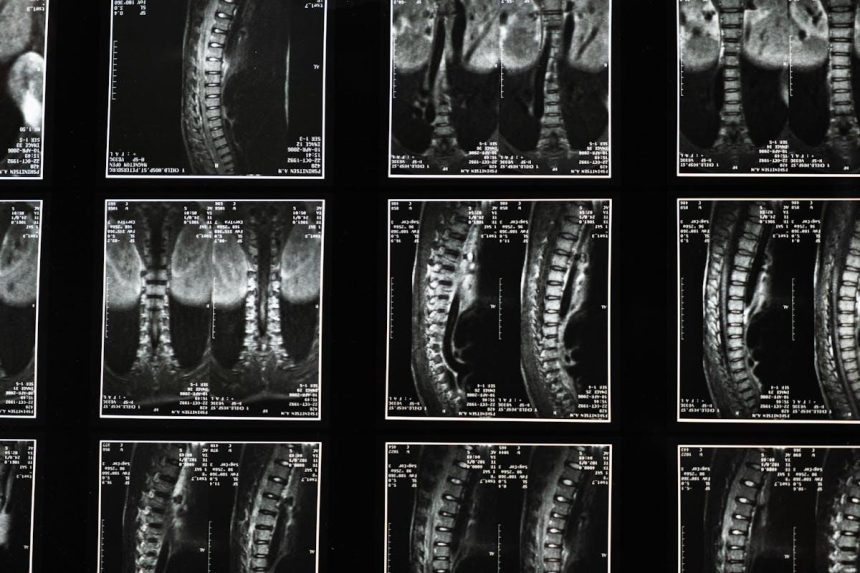

Medical records form the foundation of any spinal injury claim, but not all medical documentation carries equal weight. Emergency room records from immediately after the accident establish the injury timeline and initial severity assessment. Diagnostic imaging — MRIs, CT scans, and X-rays — provides objective evidence of structural damage that’s difficult for insurers to dispute. Treatment notes from physical therapy, pain management, and orthopedic specialists document the injury’s progression and response to various interventions.